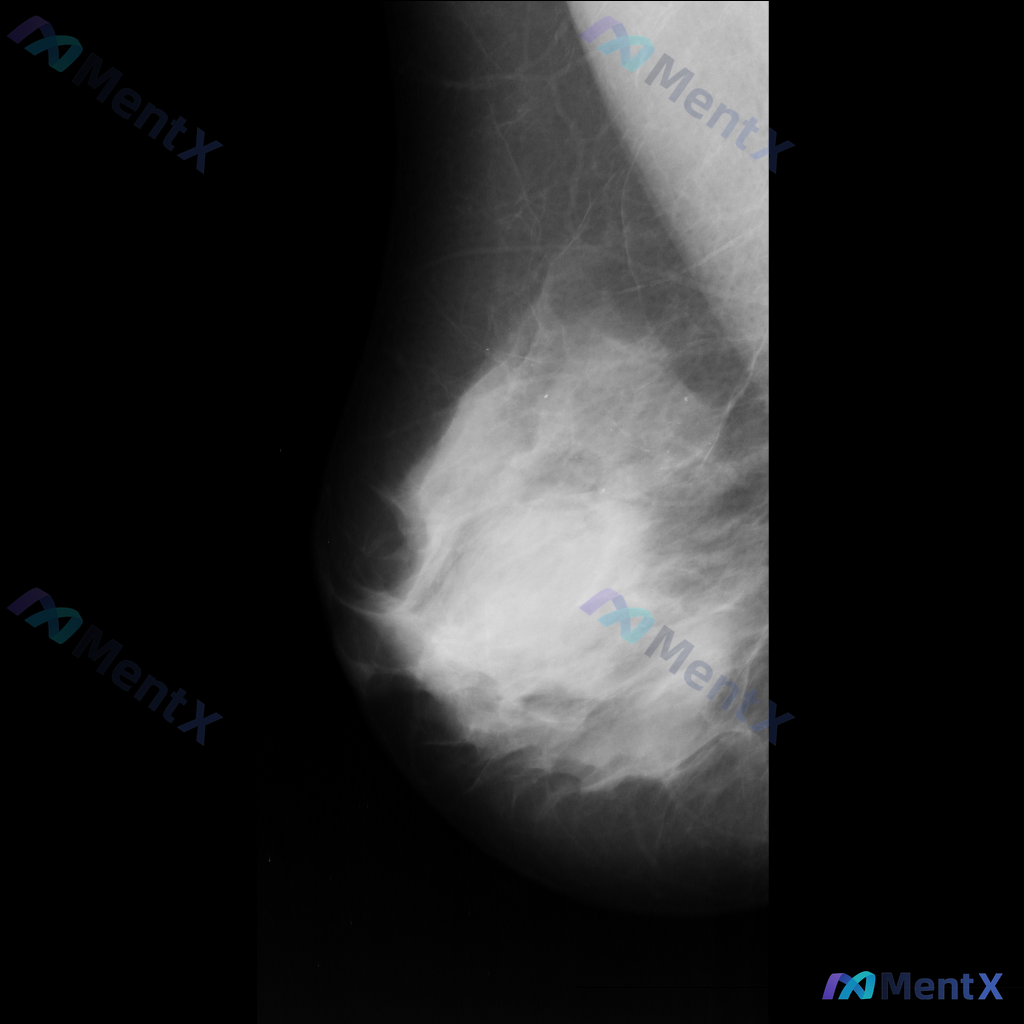

整理到一张乳腺钼靶影像的分析资料,先和大家同步一下核心表现: - 乳腺构成:不均匀致密型 - 主要异常:在乳腺中央偏上区域可见一个不规则形高密度肿块,边缘有毛刺样改变;围绕这个高密度影,周围的乳腺小叶和导管结构紊乱,向病灶中心牵拉。 目前暂时没有更多临床病史、查体或其他检查补充。想先问一下大家:单看...

整理到一组乳腺钼靶的影像资料,大家先一起看看: 影像表现: - 病灶位于乳腺上中部(大致外上象限)可见一局限性高密度肿块影 - 形态不规则,边缘有毛刺状改变 - 周围腺体结构有扭曲、牵拉征象 - 肿块内部或附近可见点状钙化,部分呈簇状分布 目前只有这组钼靶表现,大家先不补充更多临床信息的话,大家更倾...